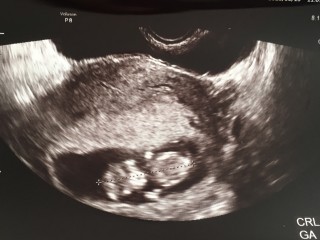

2週間ぶり&母子手帳を貰ってから初の検診!! 2週間前に見てもらった時もお医者様に 「少し大きめだね」と言われたので今回はどうなのかドキドキしながらエコーをしましたら1週間ほど大きいみたいです。前回より人の形になってて感動しました!! 膣の中がチクチク痛むので、それも先生に聞いて見たところ、特に異常はないとの事でした!よかったー一安心!!次は2週間後!!

足をバタバタして元気に動いている姿が見れて感動しました! CRLは32.4ミリ。人間らしくなってきて、ますます成長が楽しみです!